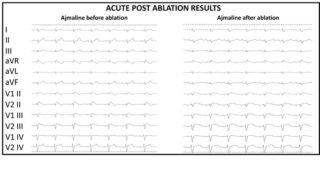

To achieve this goal, it is necessary to administer ajmaline during this mapping phase. This drug is able to unmask the cardiac electrical anomalies to the maximal degree, enabling the visualization and pronounced definition of the area of anomalous substrate to be treated.

The purpose of the ablation is to eliminate all the anomalous electric potentials located on the epicardium (figure 4), resulting in a complete normalization of the electrocardiogram which no longer shows, after ablation, the classical electrical anomalies of BrS (figure 5). These elements are also associated with the disappearance of malignant ventricular arrhythmias in post-ablation follow-up.